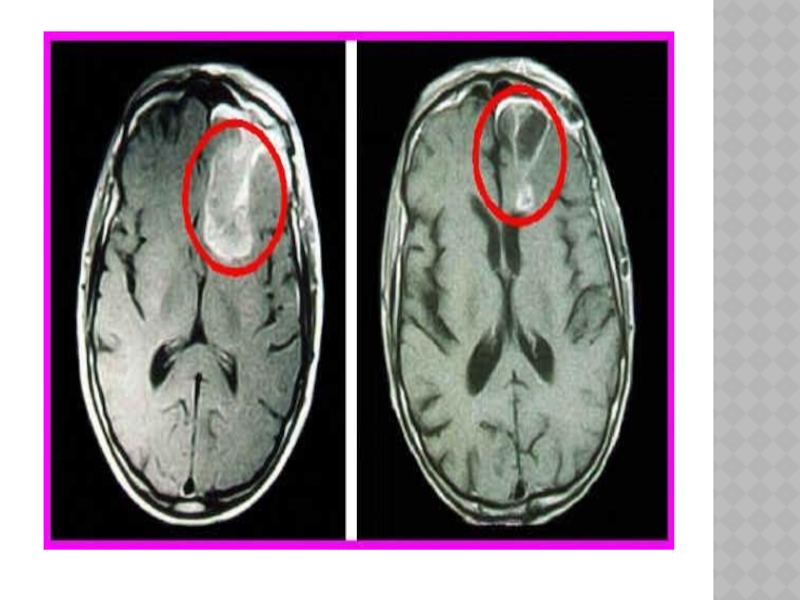

Слайд 137ЦИСТИЦЕРКОЗ ГОЛОВНОГО МОЗГА

-множественная гематогенная инвазия в мозг личинок свиного цепня.

-три

основные формы заболевания: 1).поражение больших полушарий(нарушения психики, мультифокальные эпилептические припадки, очаговые симптомамы, головные боли оболочечного характера), 2).поражение желудочковой системы(цистицеркоз желудочков мозга чаще бывает одиночным и локализуется в IV желудочке мозга, внутричерепная гипертензия, гидроцефалия боковых и III желудочков), 3).поражение основания мозга.

ЦИСТИЦЕРКОЗ ГОЛОВНОГО МОЗГА-множественная гематогенная инвазия в мозг личинок свиного цепня. -три основные формы заболевания: 1).поражение больших полушарий(нарушения

Слайд 138ЛЕЧЕНИЕ

Симптоматическое- дегидратирующие и противосудорожные средства.

Оперативное вмешательство(при доминировании в клинике окклюзионно-

гидроцефального синдрома) -удаление паразитов, разъединение сращений, восстановление или создание новых путей оттока цереброспинальной жидкости.